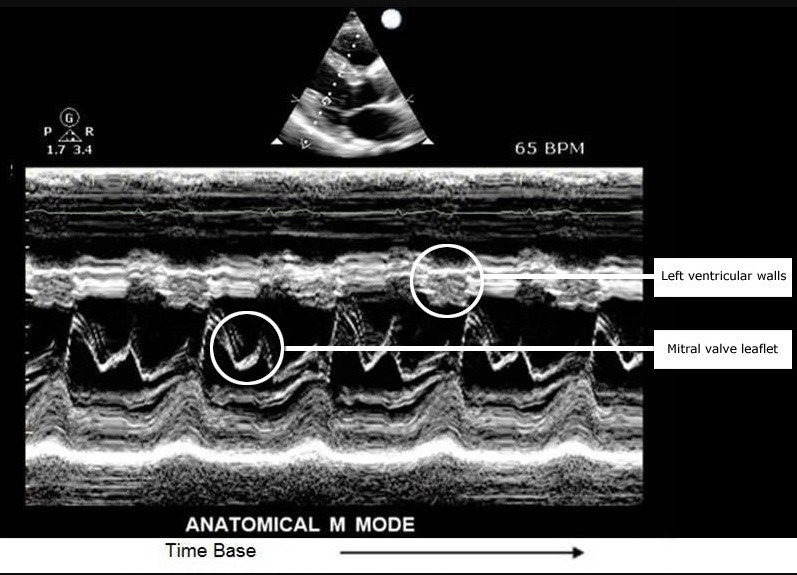

M-Mode (Motion Mode) در این مد، تغییرات مکانی ساختارهای متحرک بدن (مانند دریچههای قلب) در طول زمان ثبت میشود. محور افقی نشاندهنده زمان و محور عمودی نشاندهنده عمق است. این مد در تصویربرداری قلبی و بررسی حرکات دریچهها و دیوارههای قلب اهمیت دارد.

از نظر فیزیکی، یک پرتو ثابت به طور مداوم در یک خط خاص ارسال میشود و بازتابهای متوالی ثبت میشوند تا تغییرات حرکتی در طول زمان نمایش داده شود.